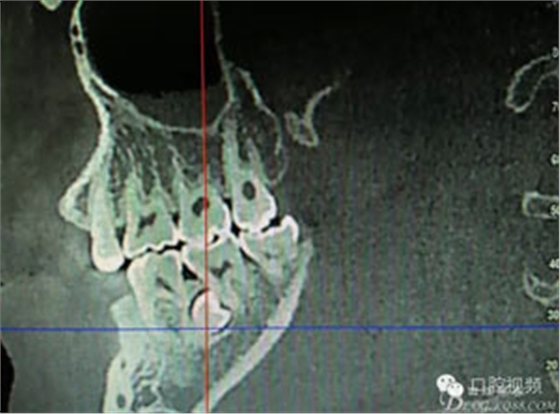

患者、盧xx、男、19歲。主訴:左側(cè)下頜乳磨牙未脫落,要求檢查。??茩z查:左側(cè)下頜第二乳磨牙有充填物。無(wú)松動(dòng),全景片檢查。35移位至36、37之間。頰舌側(cè)均不能觸及隆起。CBCT檢查:35位于36、37的舌側(cè)。表面骨質(zhì)約2mm左右。35完全骨埋伏,36的遠(yuǎn)中牙根疑是吸收。建議35暫觀察。置留不取?;颊咭蟀纬龘?dān)心壓迫36牙根或者發(fā)生囊性變。術(shù)前簽手術(shù)同意書。

圖2.術(shù)前的CBCT,35移位至36、37之間的舌側(cè)。